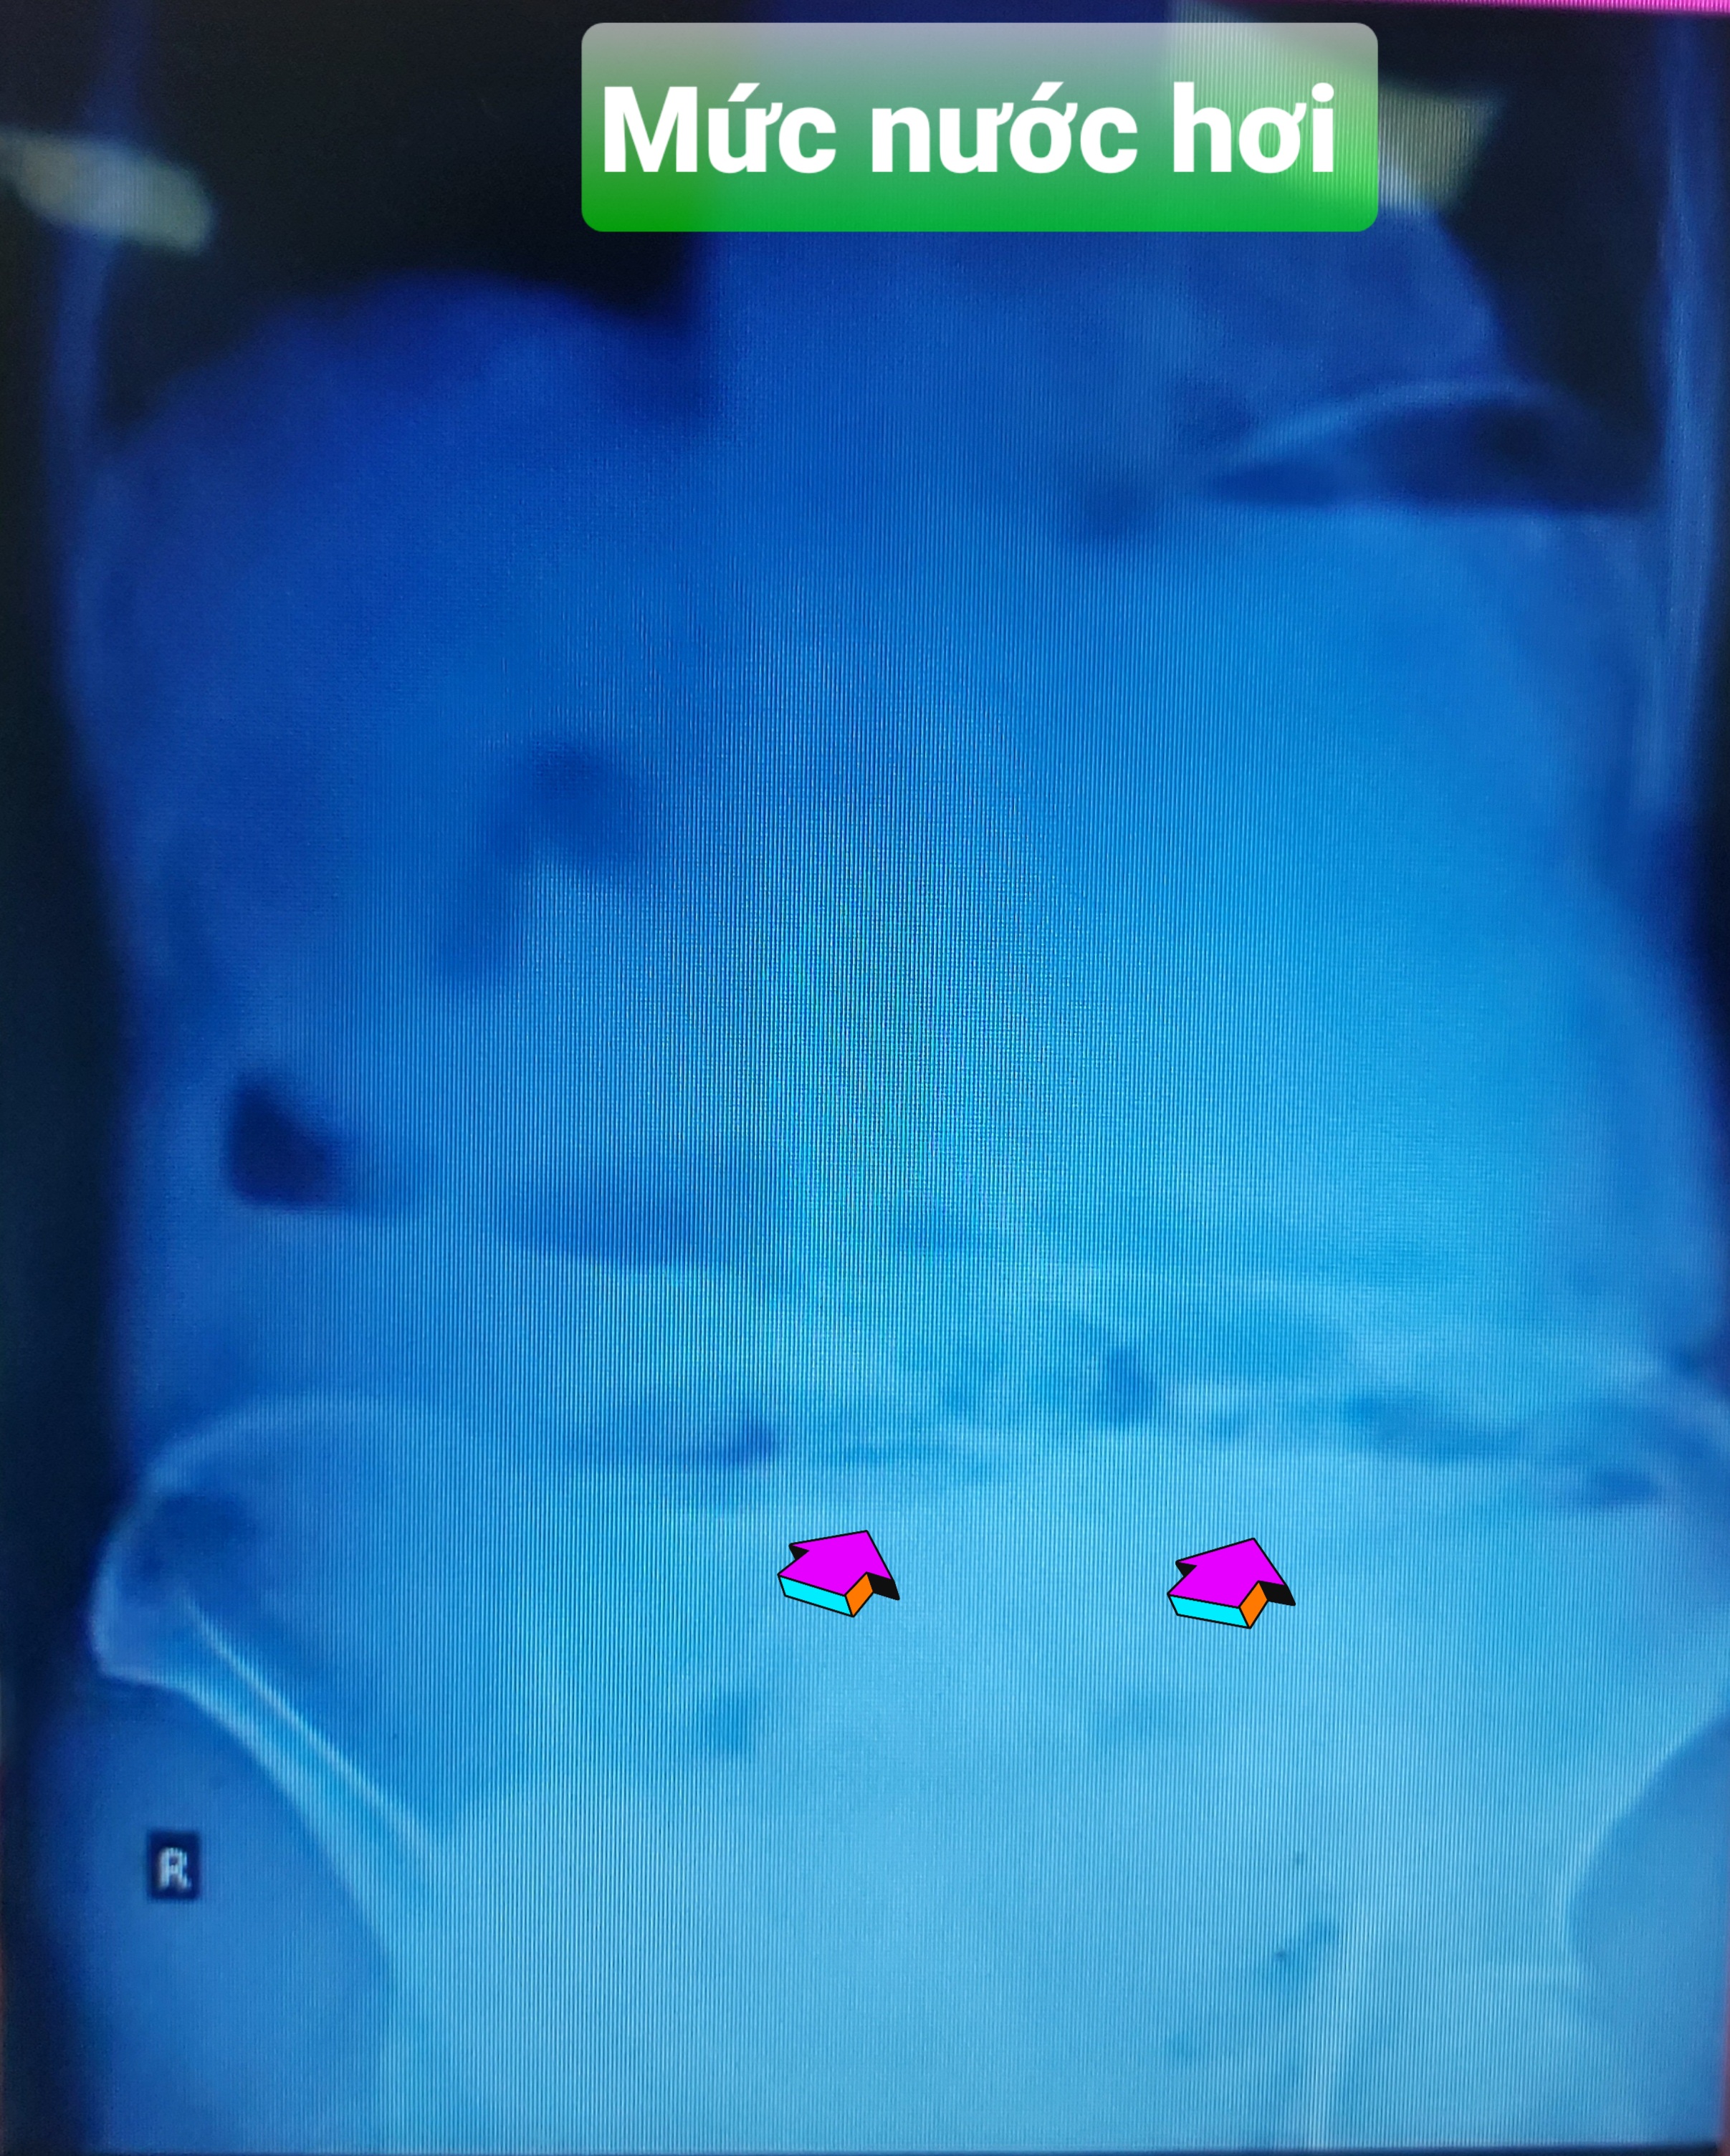

2. XQ: Hình ảnh mức nước hơi ở hạ vị - rốn.